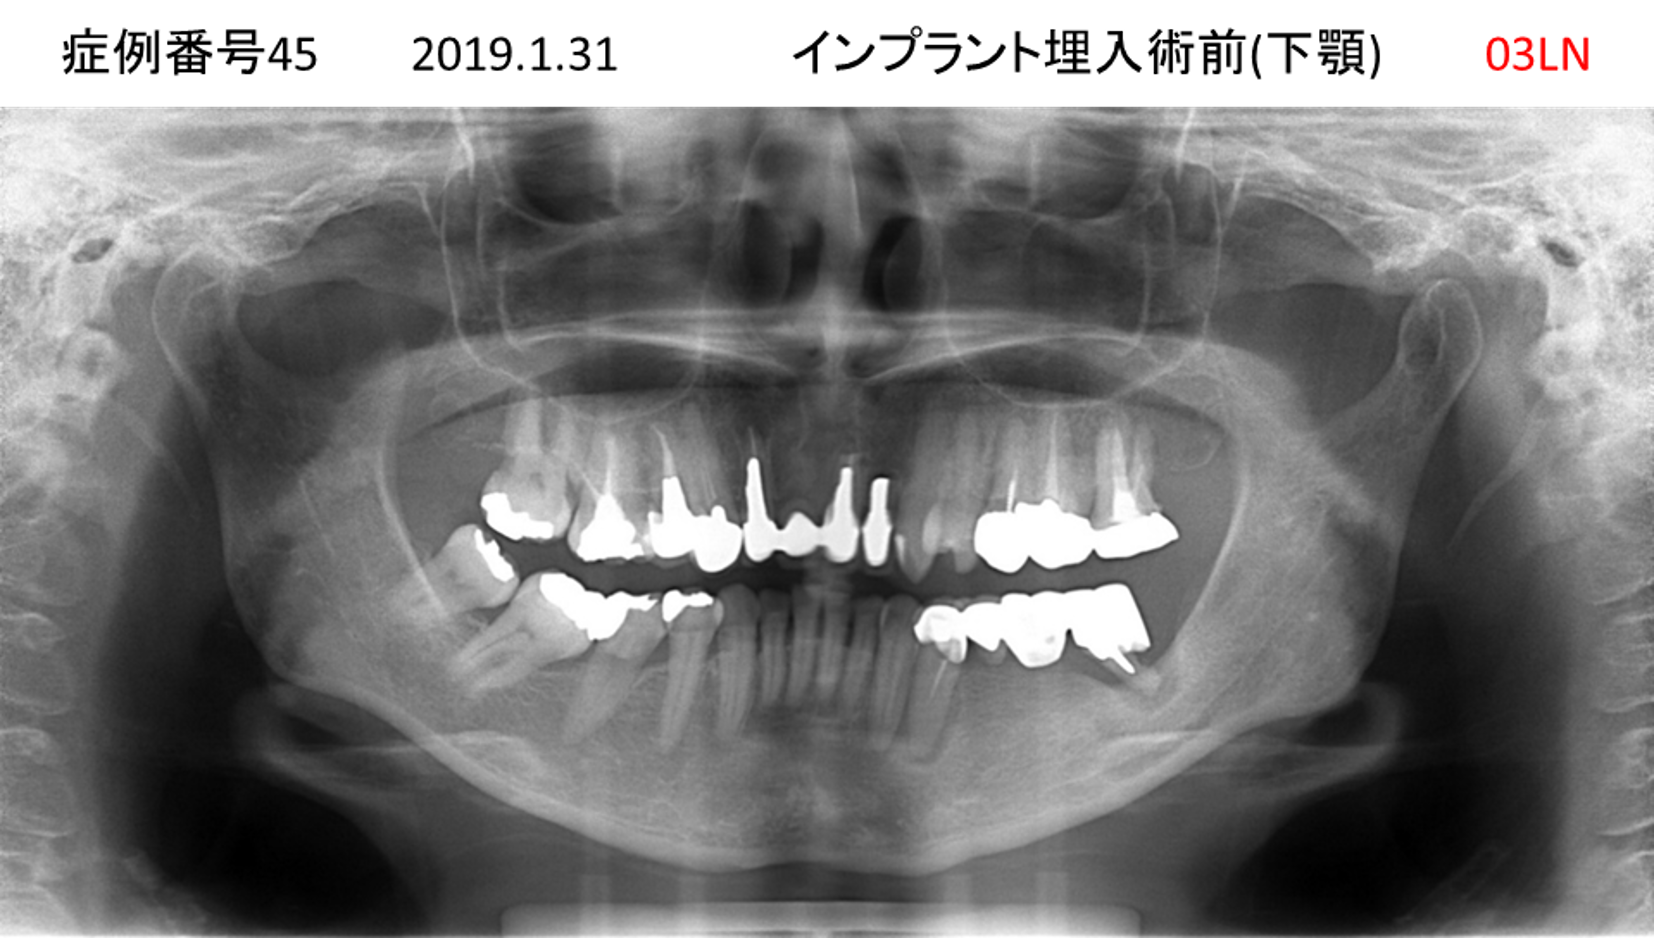

揺れている歯が多くて噛めない患者様のインプラント症例

| 治療名称 |

インプラント |

| 治療費用 |

440万円+税 |

| 治療期間 |

8か月 |

| 患者さんの症状(主訴) |

上の歯をはじめ、揺れている歯が多くて噛めない。食事ができない。 |

| 治療内容 |

サイナスリフト 抜歯即時インプラント |

| 治療結果 |

食事に困らない。見た目がとても良くなった。 |

| 治療の注意点(リスク/副作用) |

インプラントが壊れたら再治療が必要 |